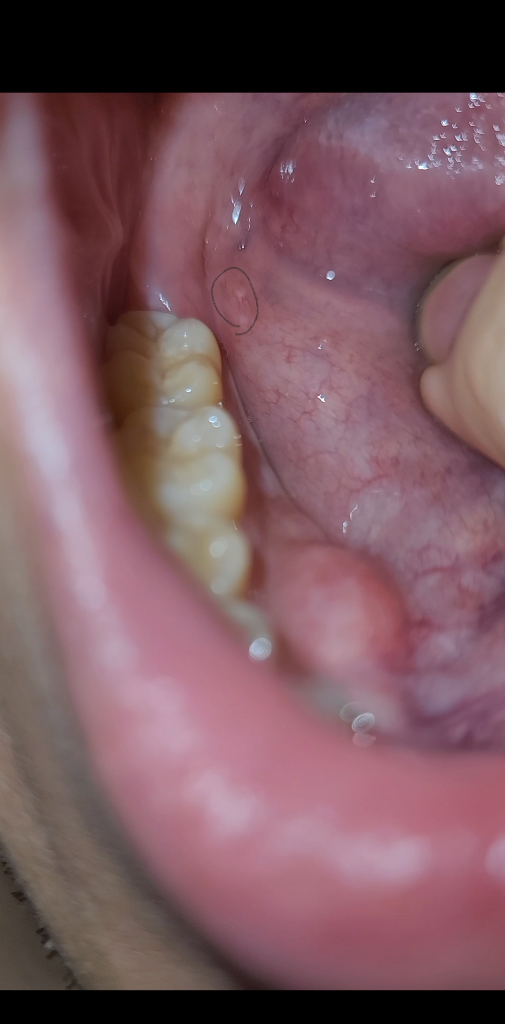

입에 뭐가났는데 구강암 일수도 있을까요ㅠㅠ?

위 사진처럼 구내염같은게 발견한지 12일째 안사라지는데 구강암일수도있나요??ㅠㅠ 술담배안하는데 너무 걱정이 됩니다ㅠㅠ

• 가능성이 절대 없다고 할 수는 없습니다만, 극히 희박하다고 볼 수 있습니다. 단순 구내염의 가능성이 훨씬 높아 보이는 소견입니다.

암이라기보다는 구내염 같습니다. 자극을 주지 않고 기다려 보시거나 약국에서 구강 연고를 사서 발라보시면 도움이 될 겁니다.